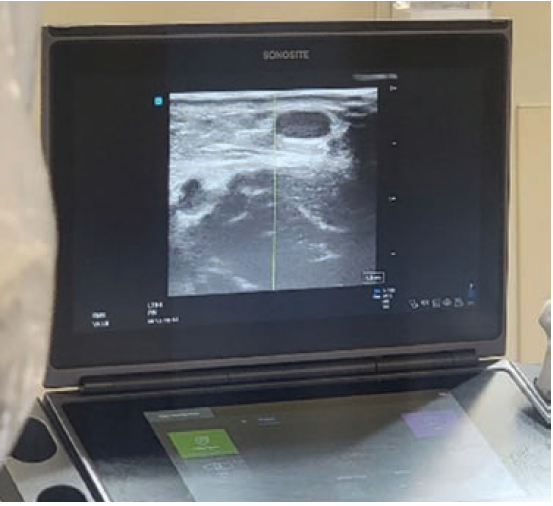

The vessel wall of a vein is thinner and not as supported by surrounding tissue, which allows the vessel to move around and dodge your needle tip. Since the venous system has a low pressure, the vessel is easily collapsable. Sometimes just the weight of the ultrasound probe is enough to collapse the vessel and make it unnoticeable (Figure 1). Similarly, just the pressure of the needle tip pushing on the top vessel wall can collapse the wall and make accessing the center of the vessel impossible.

The veins of the upper arm can be tricky in that they are not in the same spot on everyone. I have often noted that people under 200 pounds tend to have a very small or almost non-existent cephalic vein. People over 200 pounds can have vessels as deep as 3-4 centimeters from the skin’s surface. The two brachial veins take a corkscrew trajectory around the brachial artery up the arm, compounded by the fact that the brachial nerve is always in close proximity and often in the way. Some operators may go right for the basilic vein because it is usually superficial without pesky nerves or arteries in the way. Positioning the arm is pivotal in successful basilic access. It is near-impossible to get the arm in good position and also to have the patient able to hold that position for any length of time. The basilic vein tends to be low on the inner arm, requiring the angle of access to be almost perpendicular to the arm (Figure 2).